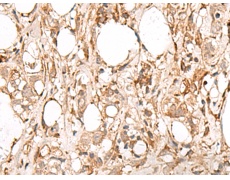

ELISA, IHC |

IHC positive control: |

Human esophagus cancer and Human breast cancer |

IHC Recommend dilution: |

50-300 |